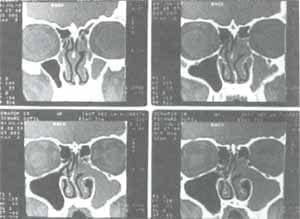

Figura 12. Tomografía computarizada con desviación septal derecha y mucocele maxilo etmoidal contralateral.

Figura 14. Tomografía computarizada practicada a paciente con septoplastia previa, con obstrucción nasal a predominio derecho, secreción posnasal y cefaleas persistentes, a pesar de la cirugía. En ella además, de observar una desviación septal de la lámina perpen-dicular del etmoides, se aprecian cornetes medios bulosos, cornetes inferiores asimétricamente resecados y engrosamiento mucoso etmoidal.

Figura 15. Tomografía computarizada con desviación septal izquierda y mucocele fronto-maxilo etmoidal del mismo lado. En estos casos, la septoplastia debe ser practicada para facilitar el acceso endoscópico a las cavidades sinusales y para facilitar el drenaje y la ventilación de las mismas en el postoperatorio.

Figura 16. Tomografía computarizada practicada a escolar de 9 años con patología obstructiva e inflamatoria sinusal, por desviación septal, hiper-trofia mucosa de cornetes inferiores y engrosamiento mucoso etmoidal.